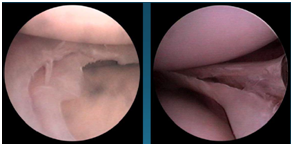

半月板损伤怎么样来修复呢,手术怎么做呢?

手术是通过关节镜来进行的,是非常微创的手术。一般两个小于1cm的切口就可以解决了。大部分患者仅适用两个小于1cm的切口,而且位于膝眼位置,

不仔细看看不出来。利用关节镜技术把损伤的半月板修整缝合加固。